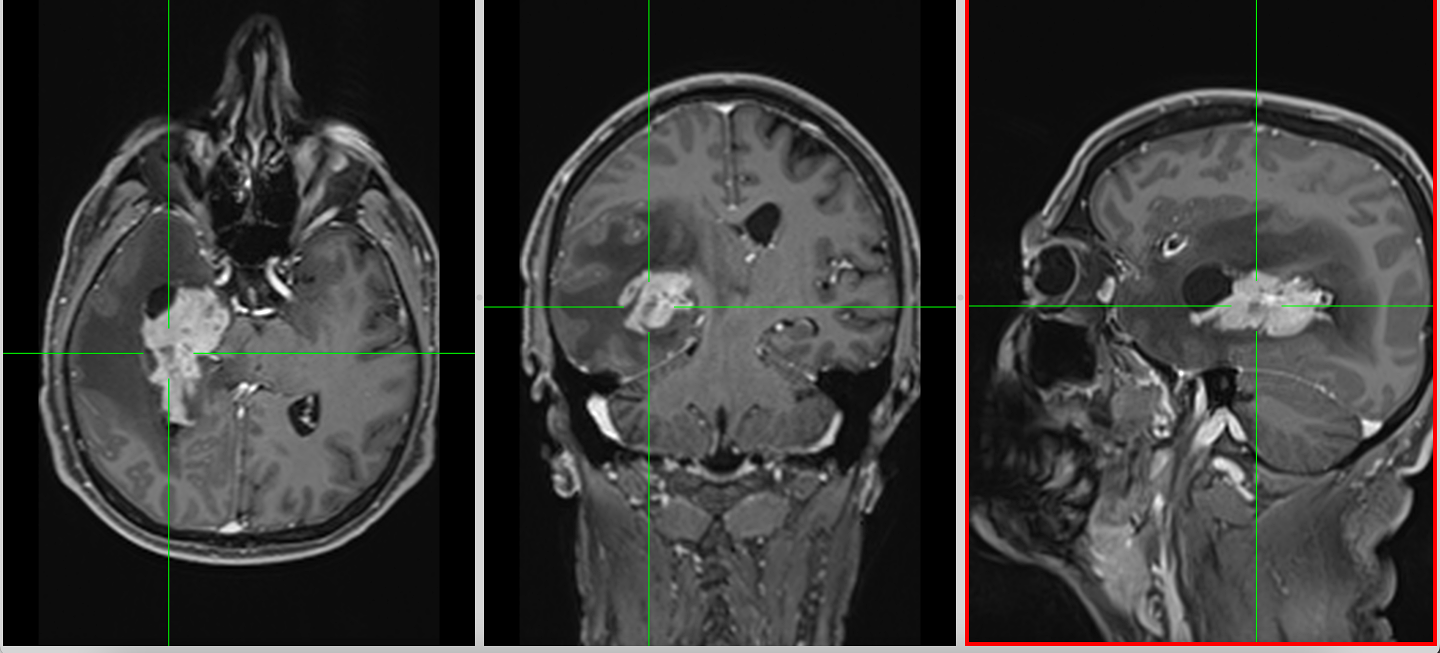

Recidiva – inevitabilitate biologică

Recidiva nu este o eventualitate, ci o etapă a evoluției bolii.

Aceasta apare de obicei:

- în vecinătatea cavității de rezecție

- rar, la distanță

La momentul recidivei, tumora este adesea:

- mai rezistentă

- mai heterogenă

- mai dificil de tratat

Opțiunile includ:

- reintervenție

- reiradiere

- chimioterapie alternativă

- studii clinice

Decizia este profund individualizată și trebuie adaptată contextului pacientului.

Etapa 7 – Recidiva

- Tratamentul în caz de recidivă trebuie particularizat în funcție de situația concretă și stabilit în cadrul unei comisii multidisciplinare formate din neurochirurg, radioterapeut și oncolog.

- Reintervenția chirurgicală – atunci când recidiva este pe locul fostei tumori sau în vecinătate (nu la distanță sau în emisferul cerebral contralateral).

- Reiradierea – atunci când recidiva este la distanță, într-o zonă care nu a fost iradiată deja.

- Chimioterapia – atunci când există recidivă tumorală sub tratament cu Temozolamida, se pot folosi citostatice de linia a doua: Irinotecan, Lomustina, Bevacizumab, PCV (Proarbazina – CCNU – Vincristina), cu rezultate mai slabe și reacții adverse mai mari. Dacă au trecut mai mult de 6 luni de la ultima cură de Temozolamida, se poate reîncepe adminstrarea ei.